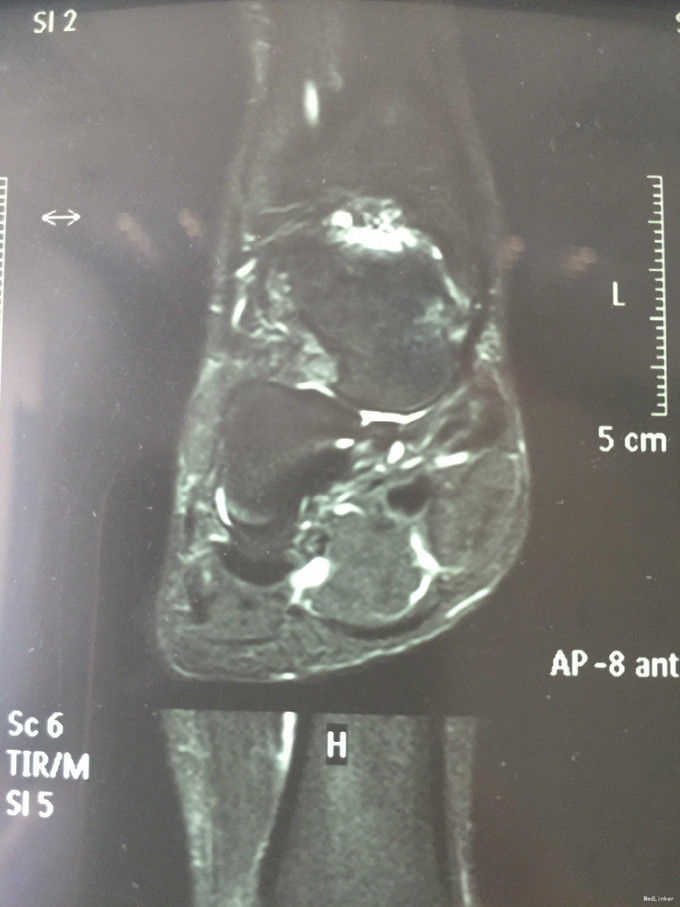

主诉:右踝扭伤后疼痛3年,伴活动受限2年。 现病史:患者男性,24岁。3年前,患者运动时扭伤右踝,无出血。患者当时至外院就诊,予消炎药物保守治疗,疼痛缓解。2年余前患者出现右踝活动受限,以背屈受限明显,伴右踝疼痛,无发热、盗汗,无其它关节痛,无晨僵等。2年来患者自觉右踝疼痛及活动受限症状逐渐加重。外院查MRI示:右胫骨远端前方骨质增生、右距骨前方骨性隆起、右踝关节内积液。我院查右踝X线示:右距骨前下方骨质密度增高、右胫骨前缘骨质增生。于我院就诊,门诊拟"右踝前方撞击综合征、右距骨骨软骨瘤、右踝滑膜炎"收入院。

查体:左下肢、双上肢肌力及活动度正常。右腓肠肌稍萎缩,右踝无明显肿胀。右踝关节跖屈、背屈受限,右踝内侧及前方关节间隙压痛(+)。ADT(-),下蹲提踵试验(+),内翻试验(-)。右腓肠肌肌力、肌张力、感觉正常。 辅查:见现病史。图片见下。

入院诊断:右踝前方撞击综合征、右距骨骨软骨瘤、右踝滑膜炎 治疗:入院完善术前检查后行右踝关节镜下滑膜清理+前方撞击成形+距骨骨软骨瘤切除。